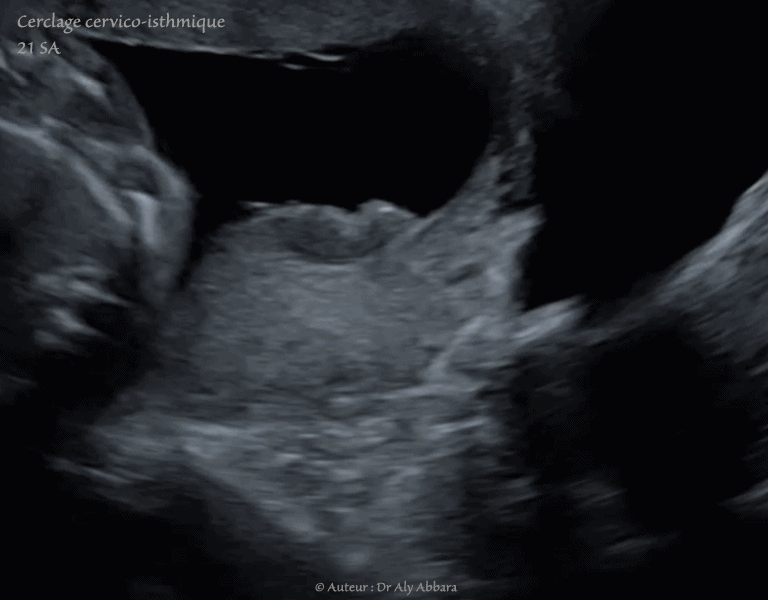

Cerclage cervico-isthmique - grossesse de 21 SA

• Images échographiques obtenues par balayage du pôle inférieur de l'utérus montrant l'aspect échographique d'un cerclage cervico-isthmique au cours de la grossesse, à 21 SA.

Il s'agit d'un cerclage par bandelette réalisé par voie abdominale cœlioscopique avant conception.

On peut constater que la bandelette ne se situe pas au niveau cervico-isthmique, mais plutôt plus bas, au milieu du col utérin, probablement par glissement au cours de la grossesse.